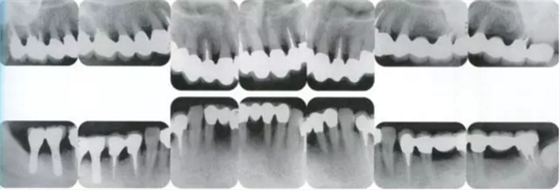

▲圖19-4

X光片。牙槽骨明顯缺失。